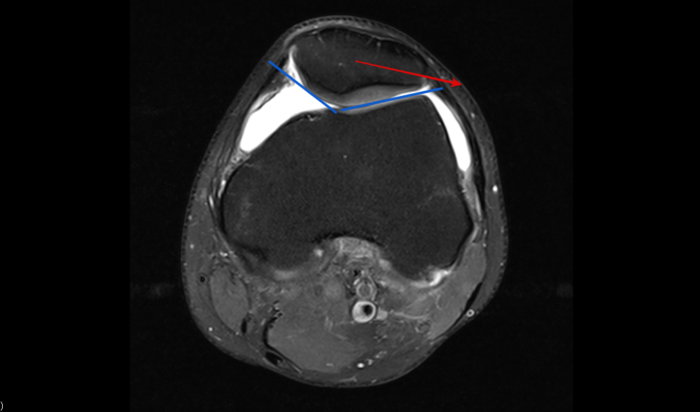

Jednym z głównych typów uszkodzenia struktury otaczającej Twoje stawy jest chondromalacja. Ta dość specyficzna choroba pojawia się zazwyczaj w obrębie stawu rzepkowo-udowego i niezwykle często ujawnia się w wynikach MRI nawet u osób nie odczuwających dolegliwości bólowych w jego obrębie.

Taki sam proces dzieje się w tkance chrzęstnej. Słaby punkt na jej powierzchni powstały w wyniku np. nieprawidłowej pracy rzepki prowadzi do „rozmiękczenia” głębszych warstw chrząstki, a proces dalszego, szybkiego uszkadzania się komórek chondrocytów to właśnie tytułowa chondromalacja. Czy można jej jakoś zapobiec?

Przede wszystkim jak już wywnioskowałaś/łeś z powyższego akapitu sama chondromalacja jest tylko skutkiem innego zaburzenia lub urazu Twojego stawu. Patrząc na staw rzepkowo-udowy zawsze warto zastanowić się co tak naprawdę jest główną przyczyną problemu. Może koślawość lub szpotawość stawu kolanowego? Może uraz chrzęstno-kostny w przeszłości, w wyniku którego przez kolejne lata doszło do uszkodzenia głębszych warstw chrząstki?

Przyczyną powstania chondromalacji rzepki może być między innymi dysplazja stawu rzepkowo-udowego lub przyparcie rzepki do kłykcia bocznego kości udowej spowodowane np. koślawością kolan.